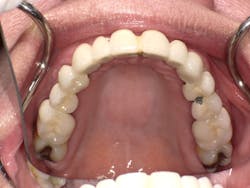

Maxillary arch prior to restorative treatment